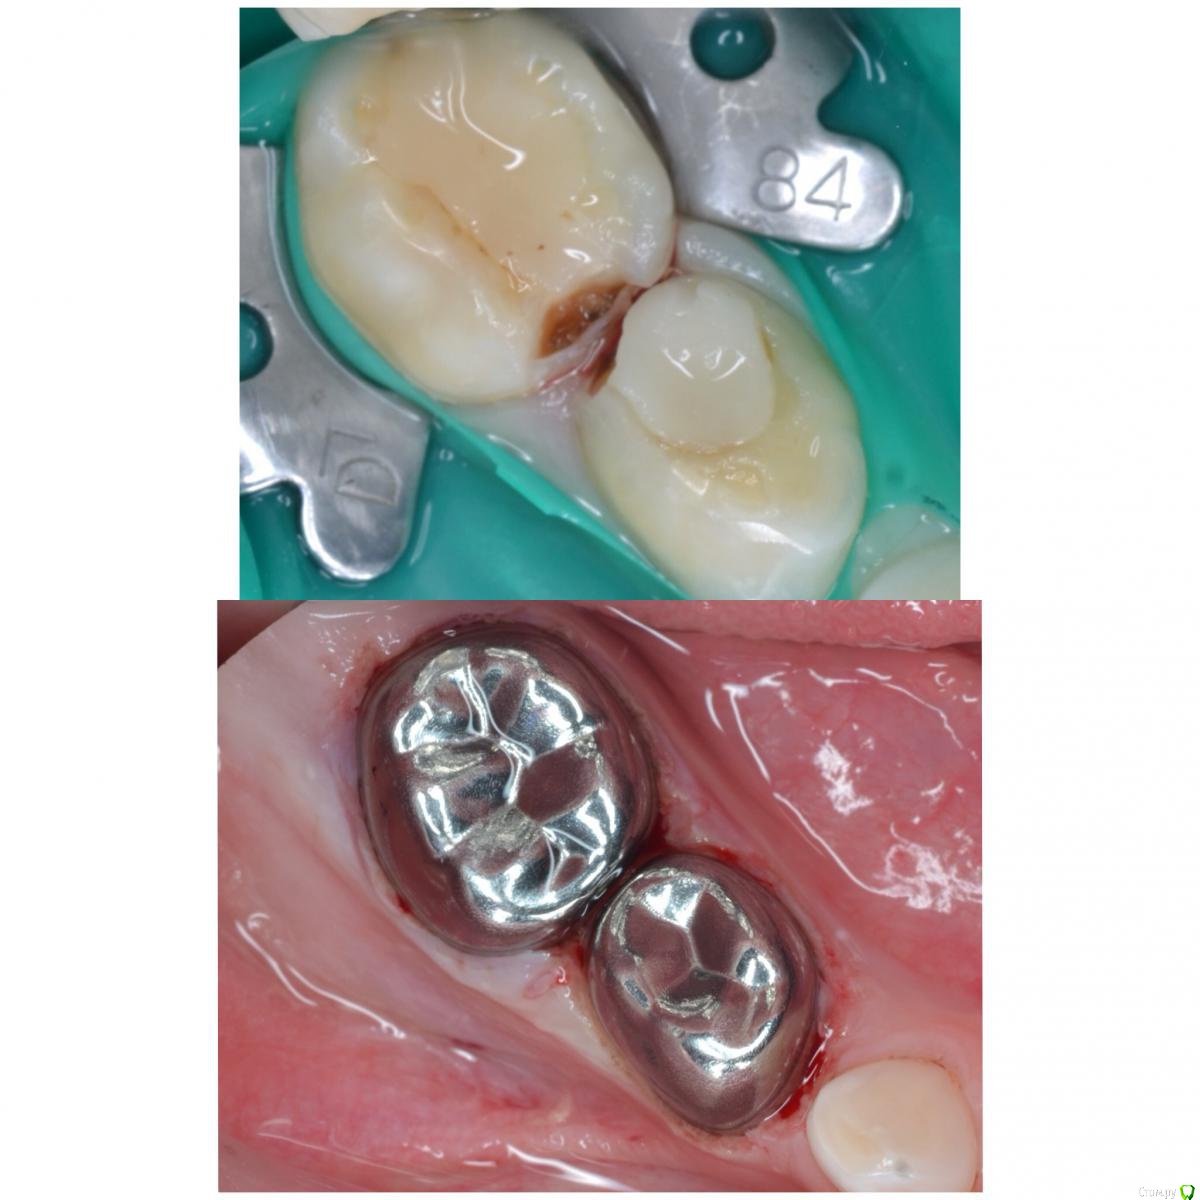

CRAZYDUCK Опубликовано 22 мая, 2018 Автор Поделиться Опубликовано 22 мая, 2018 (изменено) И про короночки ловите. 8.4 и 8.5 ранее ( около двух лет назад ) лечены методом витальной ампутации . Реставрации обширные плюс начался кариес контактных поверхностей . Два года назад я не применяла так широко в практике своей Коронки ( сейчас бы покрыла сразу после ампутации). Изменено 22 мая, 2018 пользователем CRAZYDUCK 1 Ссылка на комментарий

crown Опубликовано 22 мая, 2018 Поделиться Опубликовано 22 мая, 2018 8.4 похоже что есть изменения в бифуркации? Да надо возвращаться к коронкам. Вы где учились их ставить? Ссылка на комментарий

CRAZYDUCK Опубликовано 23 мая, 2018 Автор Поделиться Опубликовано 23 мая, 2018 В нижних 4 часто такая зона, даже в интактных. Я тоже на эту зону всегда недоверчиво смотрю. Я напишу Вам в личку позже где училась . 8.4 похоже что есть изменения в бифуркации? Да надо возвращаться к коронкам. Вы где учились их ставить? Ссылка на комментарий